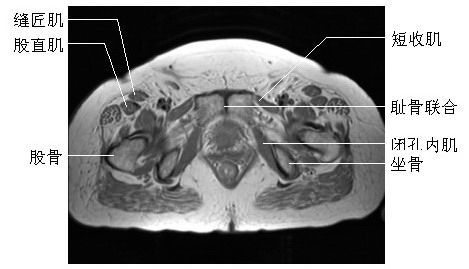

髋关节横断面(一)